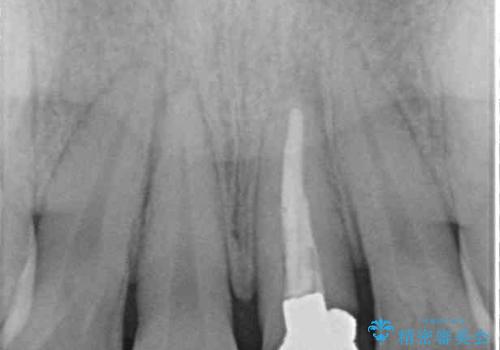

- 他院でインビザラインによる矯正治療を行っているものの、前歯の変色が気になるとのことで来院された患者様です。

インビザラインでの矯正治療がそろそろ終了とのことで、新しいインビザラインセットを発注する前に気になっている前歯2本をオールセラミッククラウンにて補綴治療を行うこととしました。

歯肉の腫脹が認められたため、仮歯へ置き換える過程で腫脹改善の指導などを行い、よりよい状態で治療を行うこととしました。